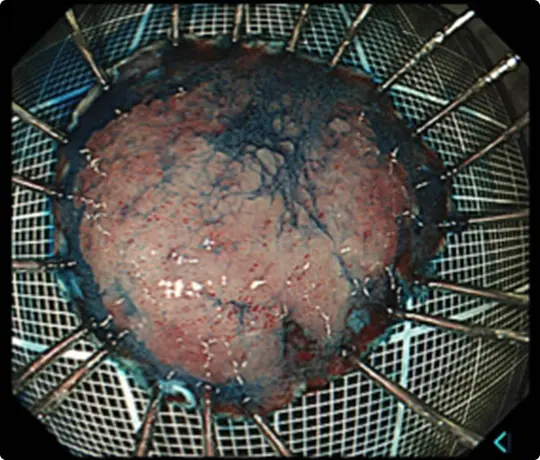

切除した検体をピンで伸ばして、ホルマリンで固定後、病理診断を行います。中央に見える赤く隆起している部分が腫瘍です(青い色素をかけています)。

病理診断で腫瘍は完全に切除されており、治癒と判定されました。